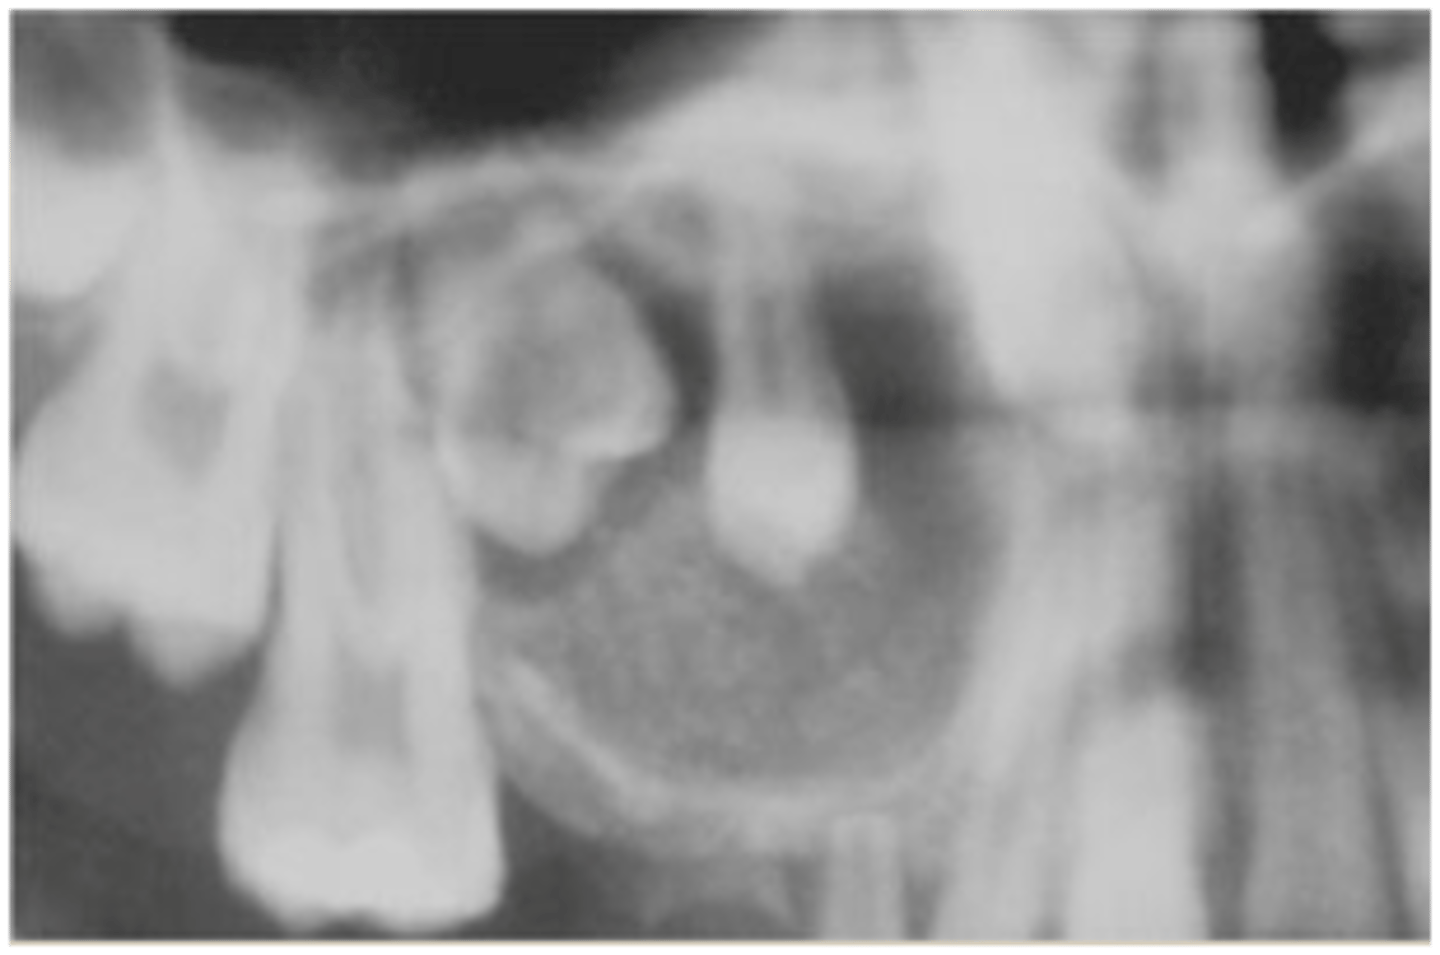

Adenomatoid odontogenic tumor (AOT) radiographically

unilocular radiolucency's with "snowflakes"

Adenomatoid odontogenic tumor (AOT)